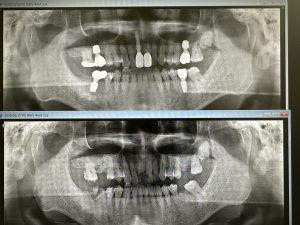

インプラント5本、内ソケットリフト2本

今後の観察は、左上下6.7番隣接の骨が如何に増えるか!?動揺はだいぶ減少している💪

EMDにCGFメンブレン使用(再生治療)